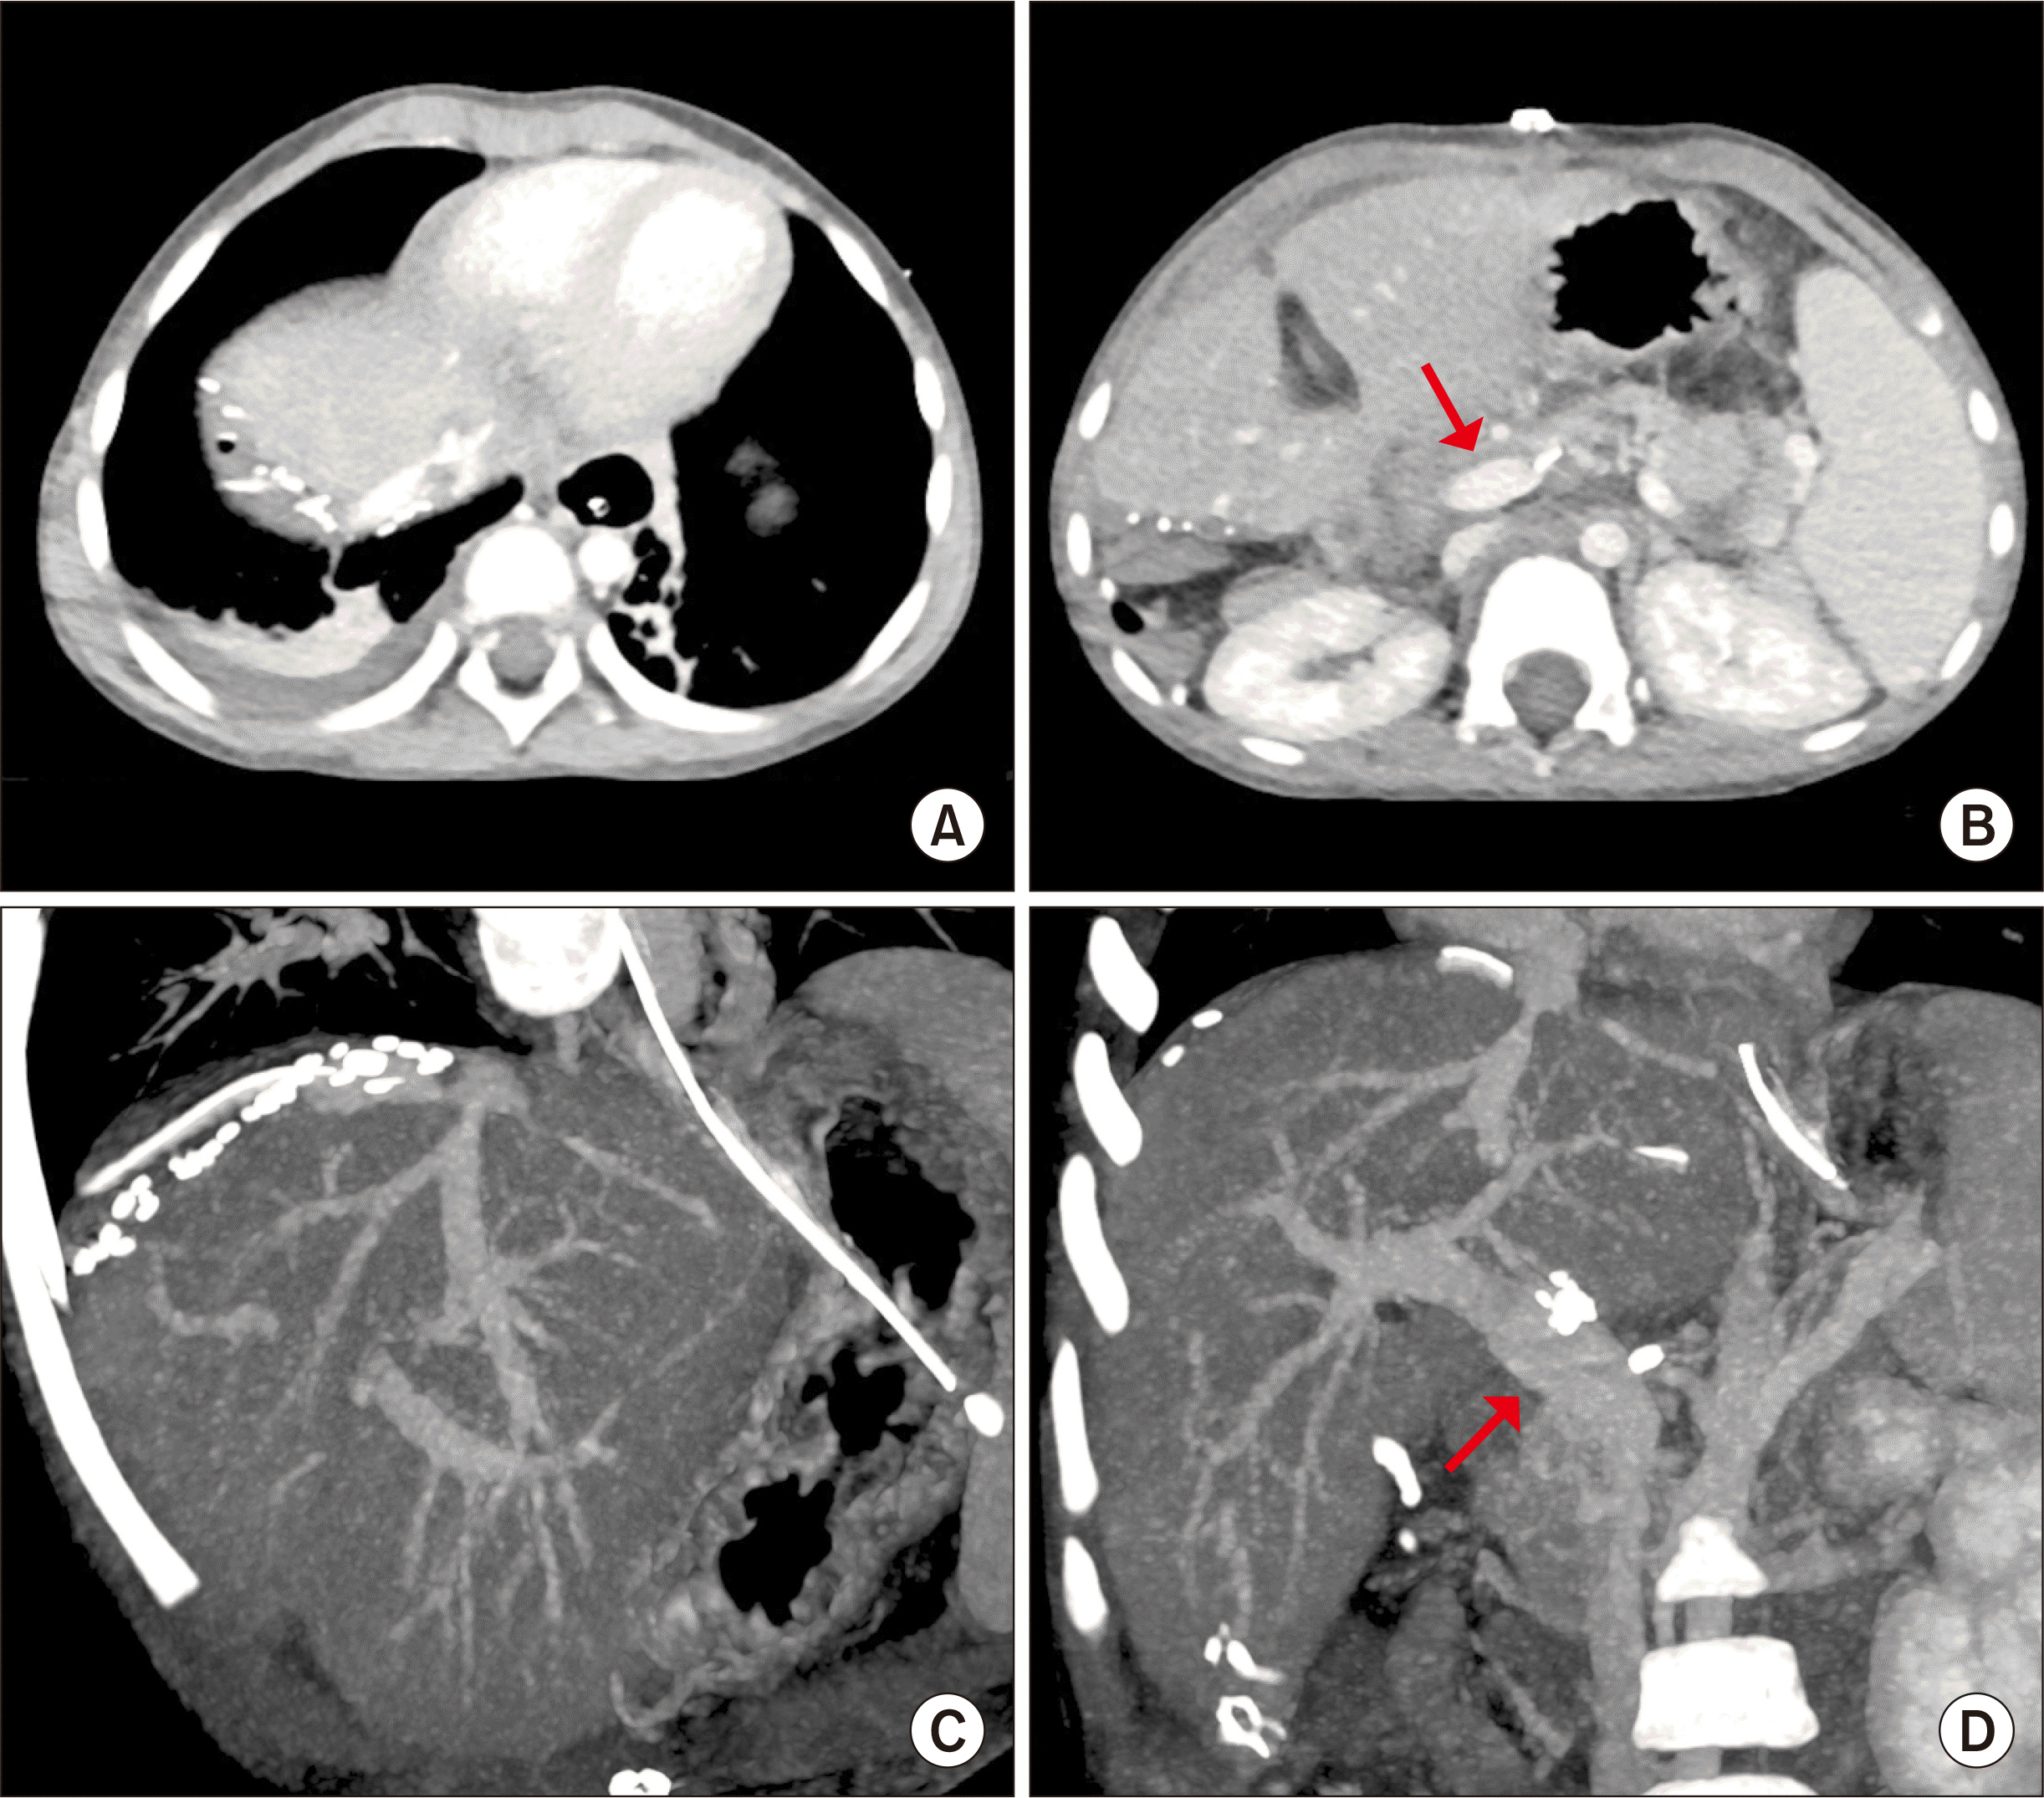

Figure 1

Preoperative computed tomography findings. (A,B) At 30 months of age, large tumors occupied the right liver. (C,D) Tumors were reduced after neoadjuvant chemotherapy and portal vein tumor thrombosis remained at the age of 34 months.